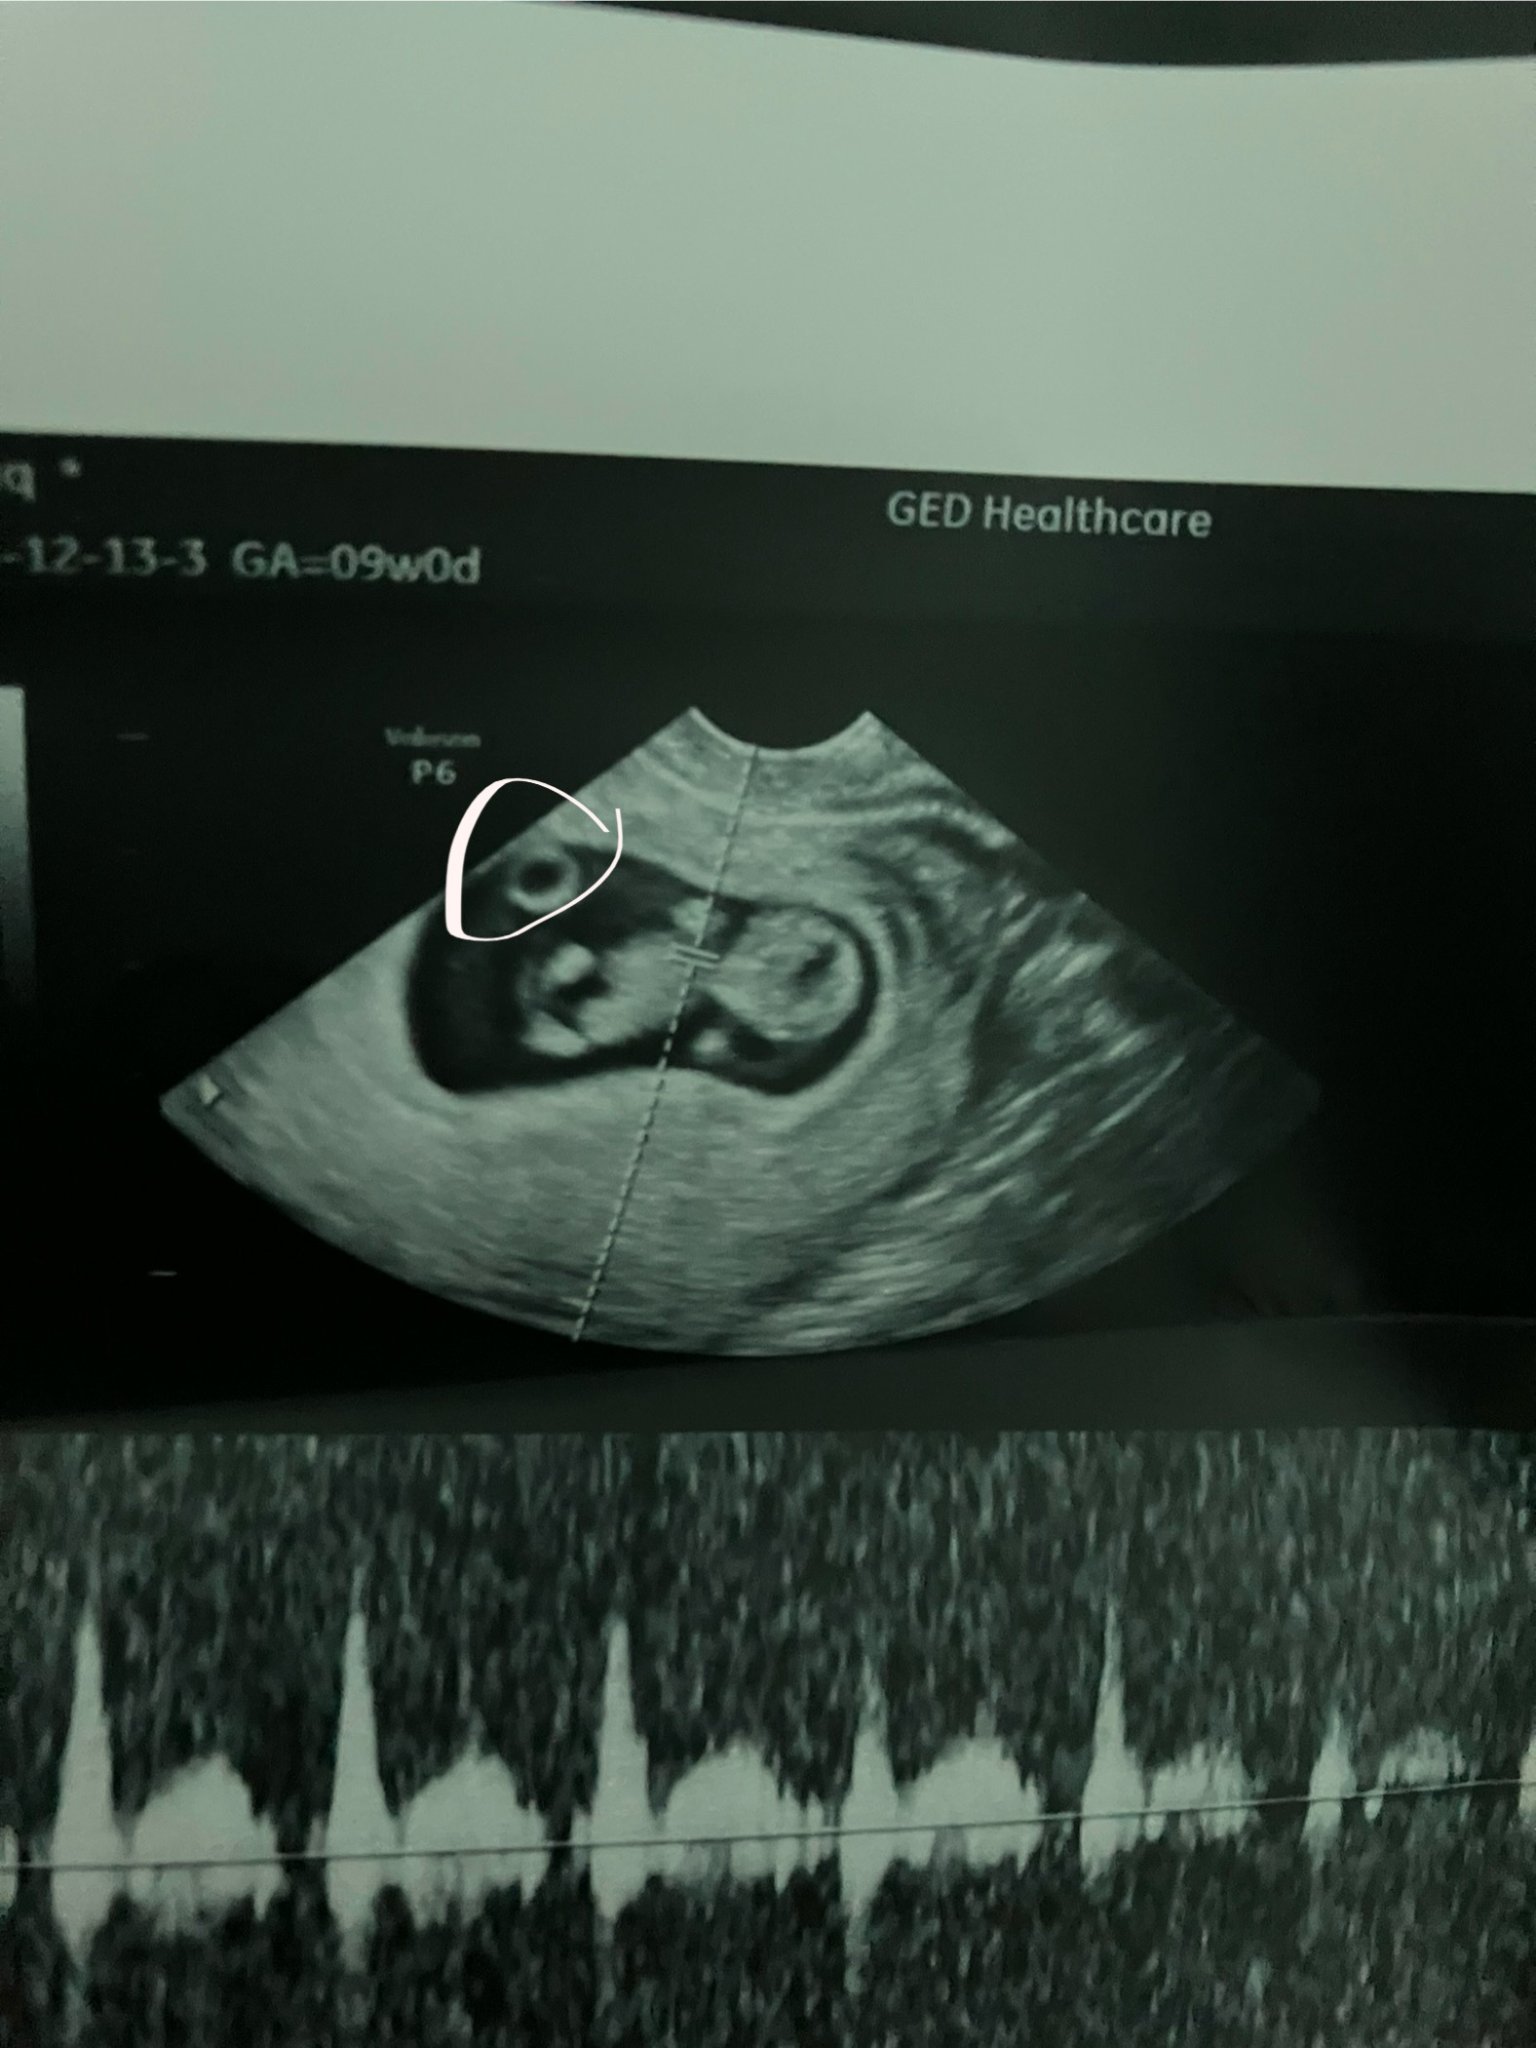

Здравейте. Днес бях на преглед и видях че има нещо някой знае ли какво е? Трябва ли да се притеснявам лекарката не каза нищо може и да не е видяла в 10г.с съм.

Нещо... Има си бебенце, това му е жълтъчното мехурче, нормално е да е там. Пийте си лекарствата и по-спокойно.